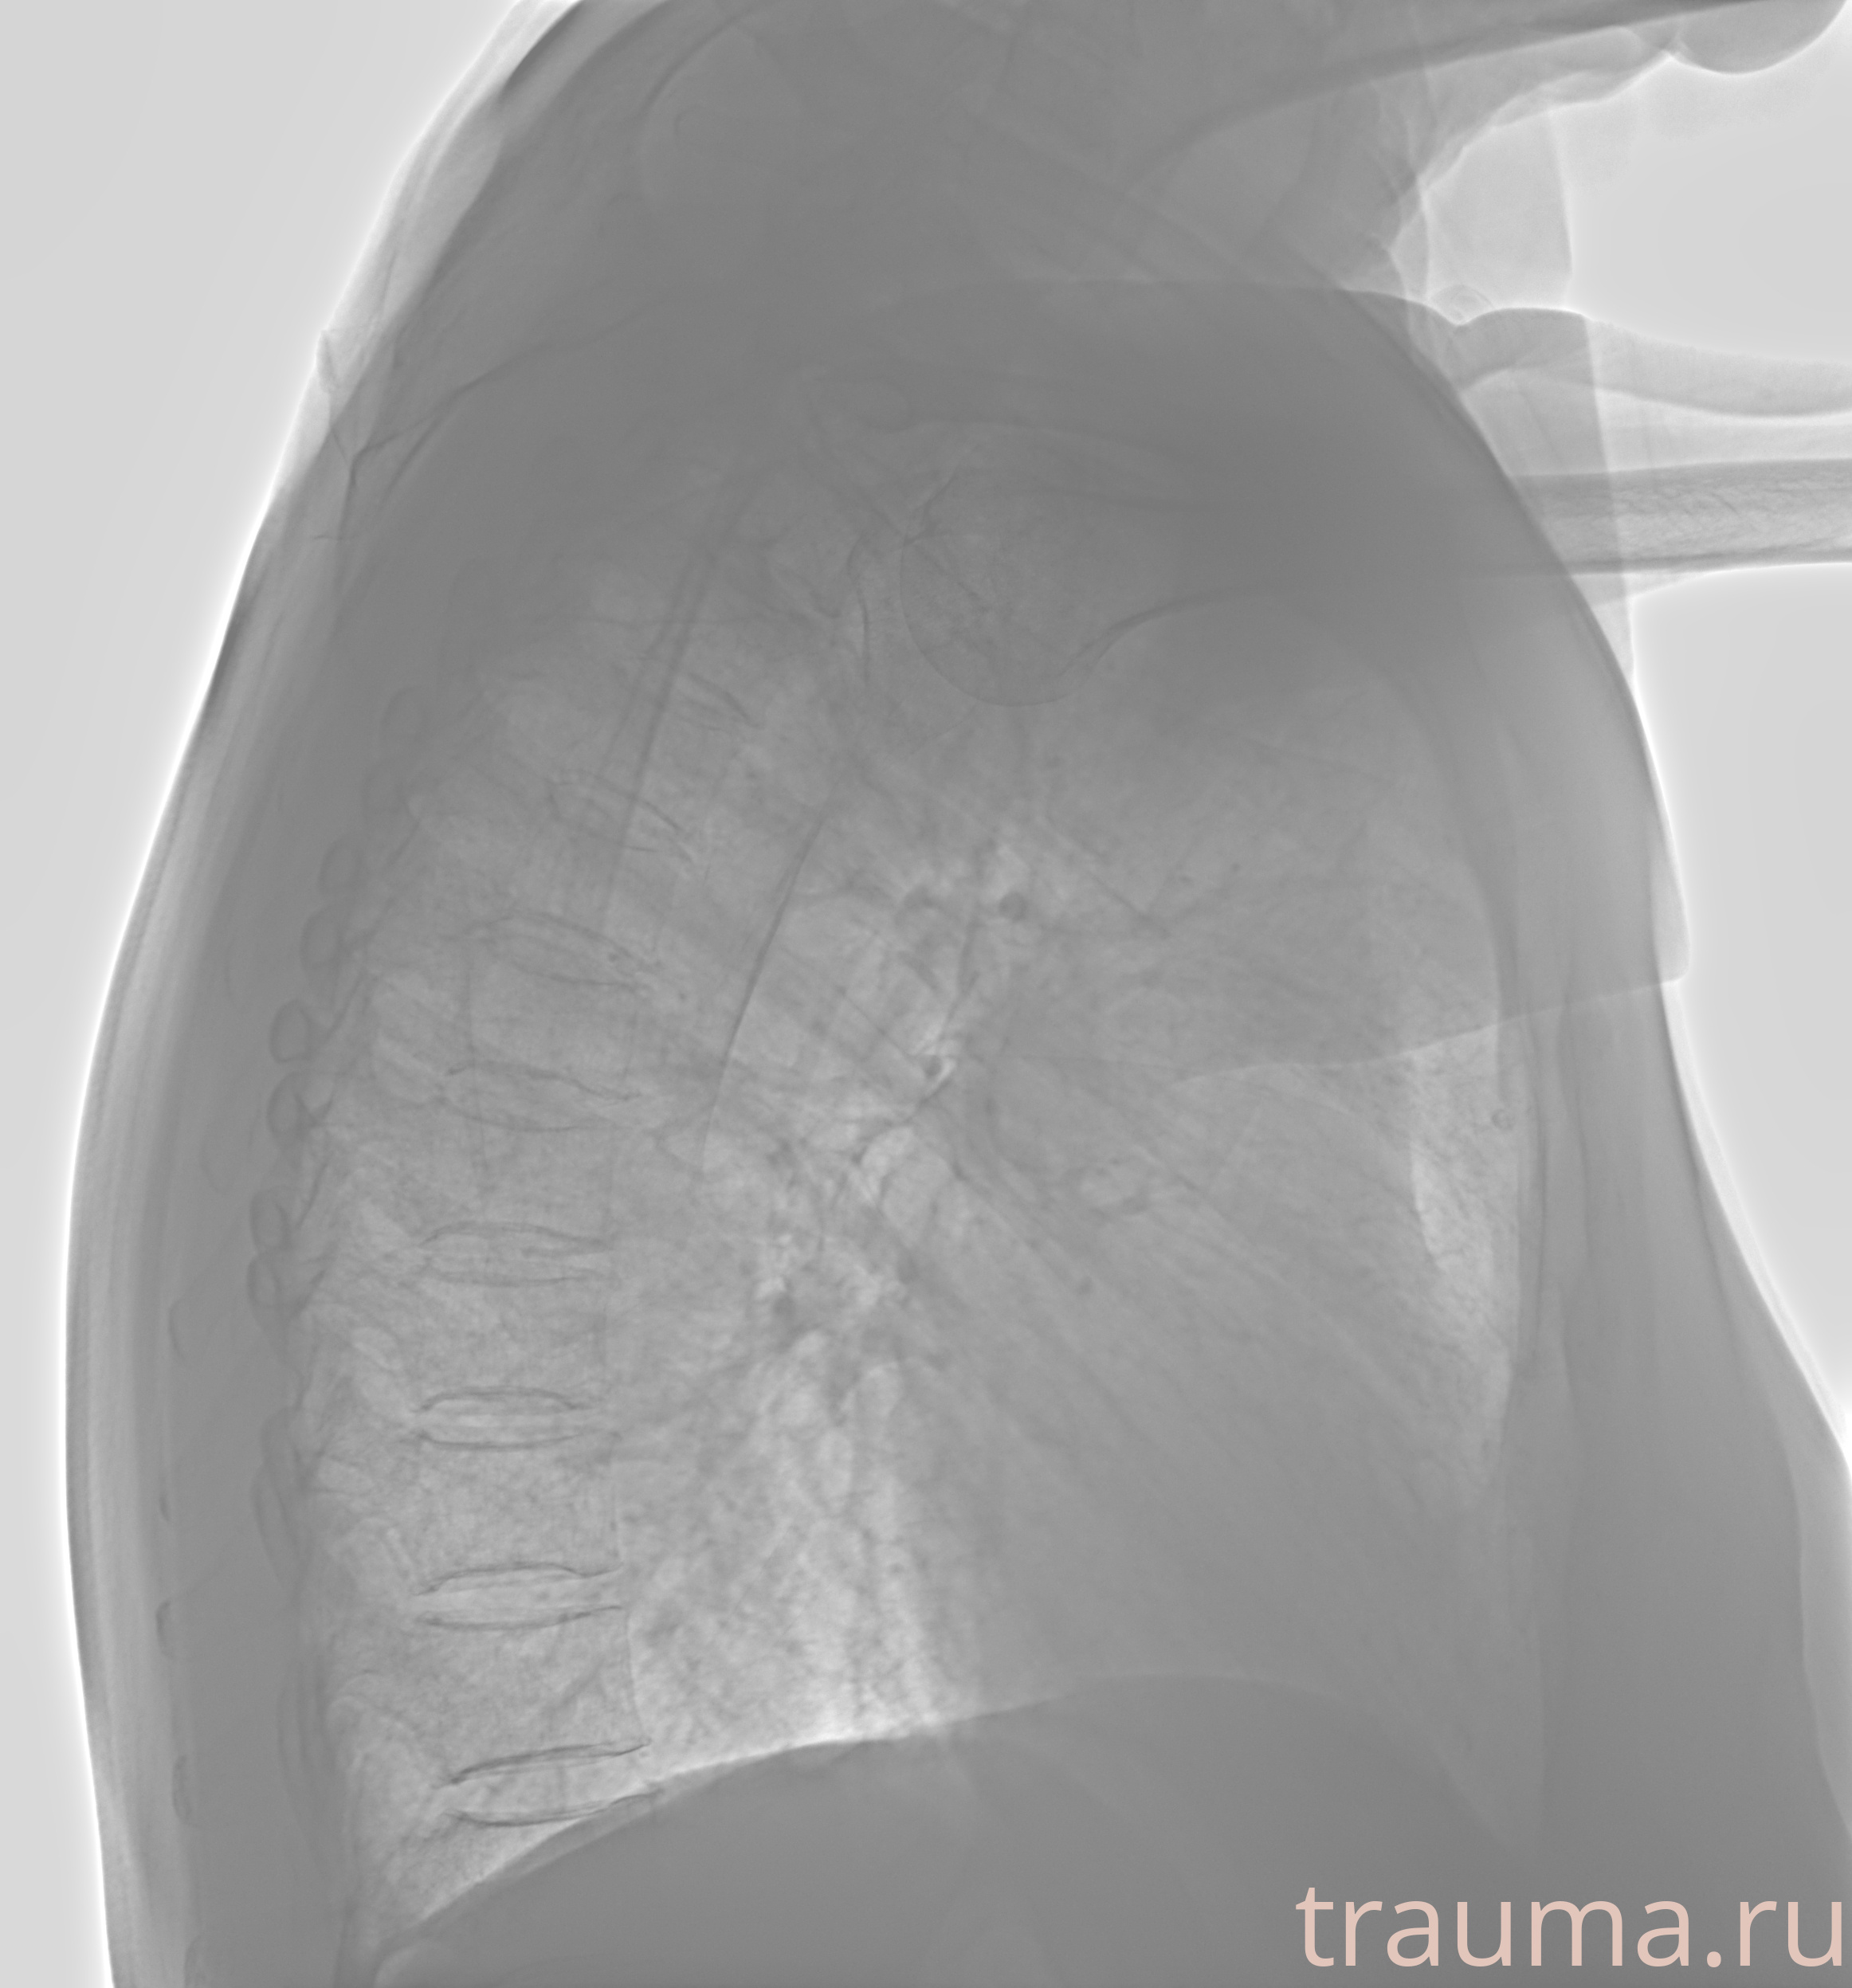

Рентгенограммы

Рентген на дому: по вашему адресу приезжает врач-рентгенолог, травматолог-ортопед с мобильным рентгеновским аппаратом, проводит диагностику травмы или заболевания, делает необходимые рентгенограммы, дает рекомендации по дальнейшему лечению. Получить качественные снимки в домашних условиях возможно благодаря уникальной методике, разработанной МосРентген Центром для института  Склифосовского